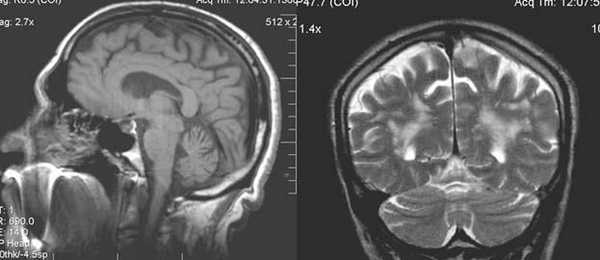

Анамнез: Юноша, 18 лет. Когнитивные нарушения, левосторонний гемипарез с раннего детства. Два эпизода судорог за последние две недели.

Описание исследования Атрофия правого полушария головного мозга с энцефаломаляцией и глиозом в смежных отделах лобной, теменной и височной долей (бассейн правой СМА), exvacuo-дилатация правого бокового желудочка, атрофия ипсилатеральной ножки мозга, базальных ганглиев и таламуса, легкая перекрестная атрофия мозжечка (левая гемисфера), ипсилатеральное смещение срединных структур и некоторое утолщение костей свода черепа.